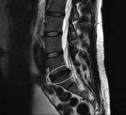

Die Bandscheiben findet man zwi-

schen den Wirbelknochen der Wirbel-

säule, und sie bestehen aus einem Binde-

gewebsring und einem weichen, gal-

lertartigen Kern. Sie „federn“ die Er-

schütterungen etwa beim Laufen ab

und ermöglichen die Beweglichkeit der

Wirbelkörper gegeneinander. Rund 90

% der Bandscheibenvorfälle gibt es im

Bereich der unteren Lendenwirbel. We-

niger häufig ist die Halswirbelsäule,

noch seltener die Brustwirbelsäule be-

troffen. Fehl- oder Überbelastungen be-

günstigen Bandscheibenprobleme. Dazu

gehört jahrelanges schweres Heben mit

falscher Technik ebenso dazu wie tägli-

che, stundenlange Fehlhaltungen, etwa

am zu niedrigen Schreibtisch am Com-

puter. Sie drücken die Wirbel in eine un-

gesunde Position.

Meist beschwerdelos

Viele Bandscheibenvorfälle verursa-

chen jedoch keine Beschwerden. Sie wer-

den zufällig bei Röntgenuntersuchungen

entdeckt. Es kommt erst zu Schmerzen,

wenn der Vorfall oder die Vorwölbung

der Bandscheibe auf empfindliches Ner-

vengewebe drückt. So reicht bei den

meisten Bandscheibenvorfällen eine kon-

servative Therapie aus. Bei Symptomen

über mehrere Wochen sollte an einen

chirurgischen Eingriff gedacht werden.

Eine sofortige Operation ist notwendig,

wenn schwere Lähmungen vorliegen

oder Lähmungen zunehmen.

Viele Bandscheiben-

Vorfälle oft unerkannt

Die Schmerzen bei einem Bandscheibenvorfall sind meist schmerz-

los. Deshalb werden die Vorfälle nicht immer entdeckt. Doch sie kön-

nen auch unerträglich sein. Im Alter von 30 bis 60 Jahren treten die

Probleme mit den Bandscheiben meist auf.

Bandscheibenvorfälle sind meist

schmerzlos. Aber sie können auch

extrem schmerzhaft sein.